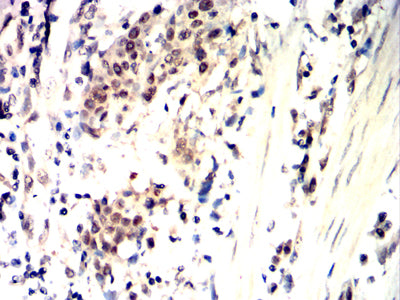

Immunohistochemical analysis of paraffin-embedded human esophageal cancer tissues using CDK4 mouse mAb with DAB staining.

Immunohistochemical analysis of paraffin-embedded human ovarian cancer tissues using CDK4 mouse mAb with DAB staining.